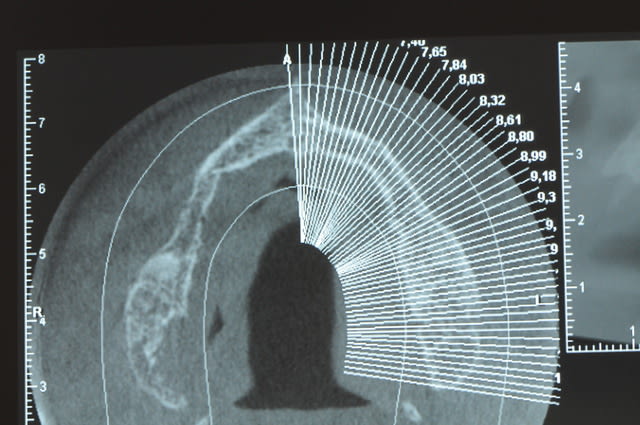

Une petite étude de ton cas D57

Sous réserves bien sur de voir l’animal en vrai

Les zones exploitables radiologiquement parlant:

Coupes implant

2,3 40100

4,96 35130 avec sinus lift mais difficile

5,25 35150

6,02 35130

6,78 35115 après réduction de hauteur de crête

7,26 35115 après réduction de hauteur de crête

8,51 35150

10,43 40115 ou 50115

11,10 40115

Ce qui nous fait 9 implants possible évidement avec un comblement de sinus on augmenterait encore les zones implantable mais ce n’est pas le but recherché, avec 8 (4+4) il doit être possible de faire une belle barre support de complet